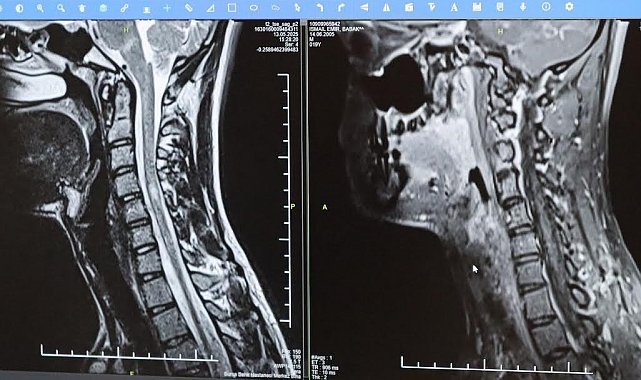

Bursa Şehir Hastanesinde görevli Nöroloji Uzmanı Prof. Dr. Özden Kamışlı, 30 Mayıs Dünya MS Günü kapsamında açıklamalarda bulundu. MS'in, bağışıklık sisteminin sinir sistemine saldırmasıyla gelişen kronik bir hastalık olduğunun bilgisini veren Prof. Dr. Kamışlı, "Dünyada yaklaşık 2.8 milyon MS hastası olduğu bilinmektedir. MS genellikle 20-40 yaş arası gençleri etkilemektedir. Bununla birlikte çocukluk döneminde ya da ileri yaşta da ortaya çıkabilmektedir. Kadınlarda görünme sıklığı erkeklere göre bir buçuk kat daha fazladır" dedi.

MS hastalarının çeşitli şikâyetlerle hekimlere başvurduğunu vurgulayan Kamışlı, "Bunlar arasında görme bozukluğu, kol ve bacakta kuvvetsizlik, uyuşmalar, dengesizlik, yürüme bozukluğu, idrar problemleri veya aşırı yorgunluk ve halsizlik hali bulunmaktadır. MS ataklarla seyredebilir ve genellikle en sık görülen formu budur. Birdenbire bir şikâyet ortaya çıkar ve zamanla azalır veya kaybolur. Bir de progresif dediğimiz ilerleyici formu vardır. Bu ilerleyici formda hastalık yavaş yavaş ilerlemektedir. MS her hastada farklı seyreder. Bu nedenle tek tip bir MS hastalığından bahsetmek mümkün değil" şeklinde konuştu.

Hastalığın tanısını ne kadar erken konulursa ve tedaviye ne erken başlanırsa; hastaların günlük hayatta aktif ve üretken bir şekilde devam etmelerinin o kadar kolaylaştığına dikkat çeken Kamışlı, "Günümüzde MS'le ilgili çok fazla gelişme oldu ve tedavi seçenekleri arttı. MS merkezlerinde bu tedavi seçeneklerine ulaşmaları mümkün. Hastalarımız için doğru tanı, düzenli takip ve uygun tedavi oldukça önem teşkil etmektedir" diye konuştu.